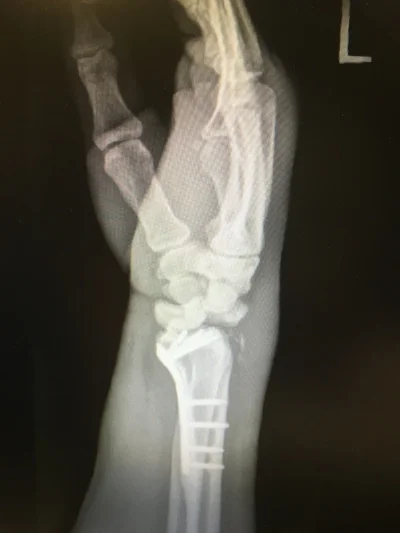

Miraculously, I ended up only breaking my wrist and having a minor concussion (too minor for Will Smith). Stillwater ER said I would be back on the bike in six weeks, but once I got a second opinion, I ended up needing surgery due to a dislocation and fracture in two places of the scaphoid.

x-ray2.jpeg